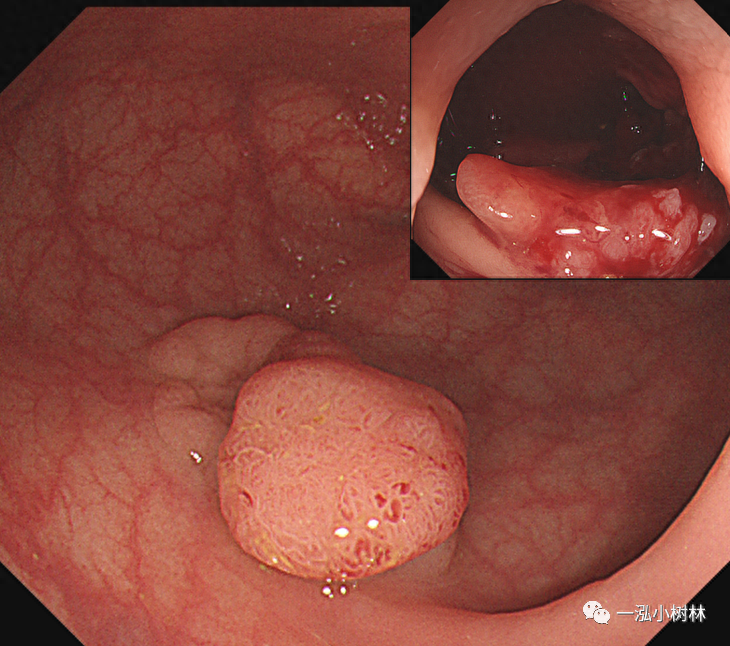

图3 结肠管状腺瘤(Pit Pattern IIIL型)

图4 结肠管状腺瘤(Pit Pattern IIIS+IIIL型)